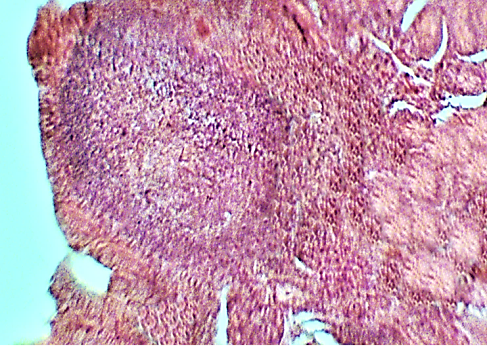

Figure 4

The mucous membranes of small (A) and large (B) intestines in cows with mild hoof lesions. Staining with hematoxylin and eosin. 100 x magnification.